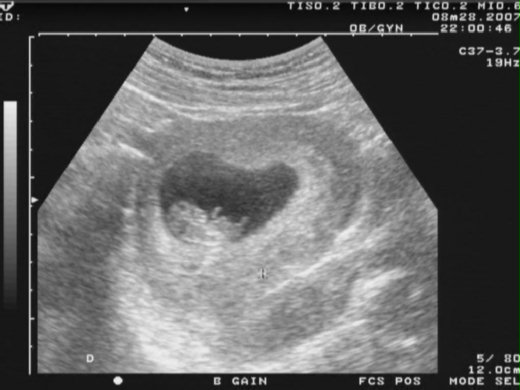

現在你已經四公分囉!長大了不少。